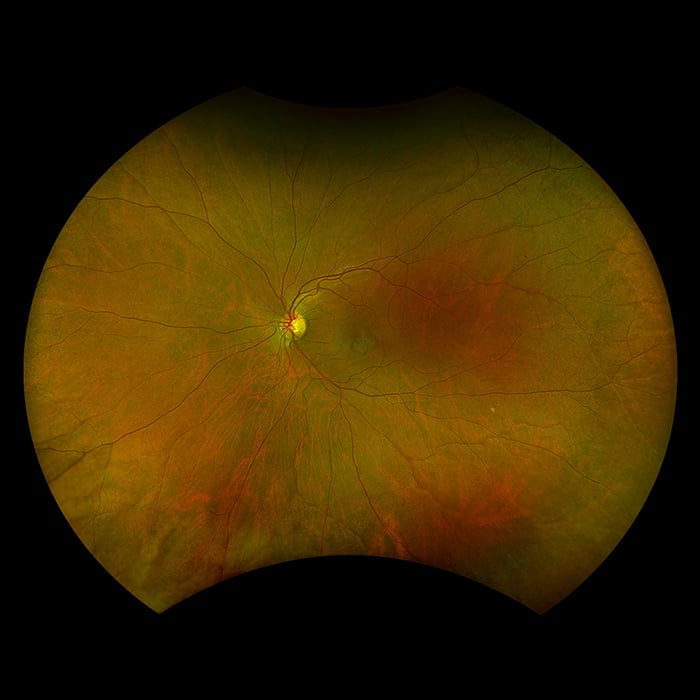

Daytona erstellt mit nur einer einzigen Aufnahme und in weniger als einer ½ Sekunde ein 200° optomap Bild der Netzhaut von unübertroffener Klarheit. Diese schnelle, einfache und patientenfreundliche Ultraweitwinkel-Bildgebungstechnologie wurde für das Screening gesunder Augen entwickelt und verbessert nachweislich den Praxisablauf und die Patientenbindung.

Daytona bietet Augenärzten digitale UWF-Bilder von 200 Grad oder bis zu 82 % der Netzhaut in einer einzigen, kontaktlosen optomap-Aufnahme. Darüber hinaus wird dasDaytona-Gerät mit der browserbasierten Bildüberprüfungssoftware OptosAdvance™ geliefert, die eine einfache Dokumentation, Überwachung und Bearbeitung von Überweisungen ermöglicht, um das Patientenmanagement zu unterstützen und den Patientenfluss zu verbessern.